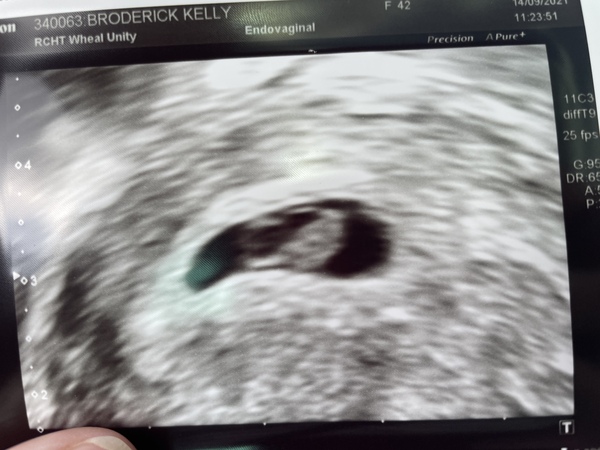

Kelb79 · 16/09/2021 00:07

Hey gang, had my scan and YAY!!! My little peanut has a strong heartbeat and all is looking great 🥰🥰🥰 I’m so so happy and relieved and can definitely relax just a little bit! Such a great feeling! 🙏🏼🙏🏼🙏🏼

maymum94 · 17/09/2021 16:25

Hey ladies I wanted to share with you my scan I had a couple days ago. We're so happy our little bean was bouncing around currently 7+ 3 the date same a day early so I definitely think I'm going to be having a April baby. Hope everyone is doing okay my sickness has been awful but I'm getting there.

Going to share my picture on the Facebook group as well as I noticed it's starting to get a few ladies there. It's so exciting there is so many of us due now. 🥰🥰